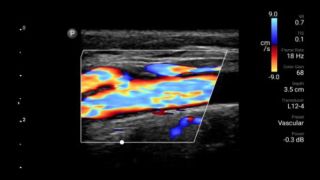

Exceptional ultrasound imaging

Lumify handheld ultrasound offers images that enhance diagnostic confidence.